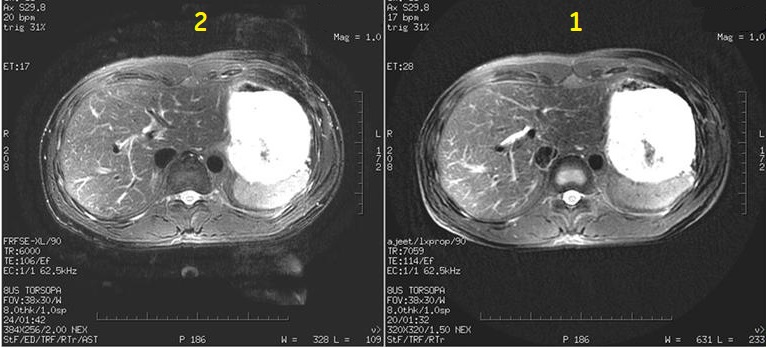

Figure 2. Motion reduction Image comparison

Table 2. Image legend

Number

Description

1

PROPELLER image

2

FSE image